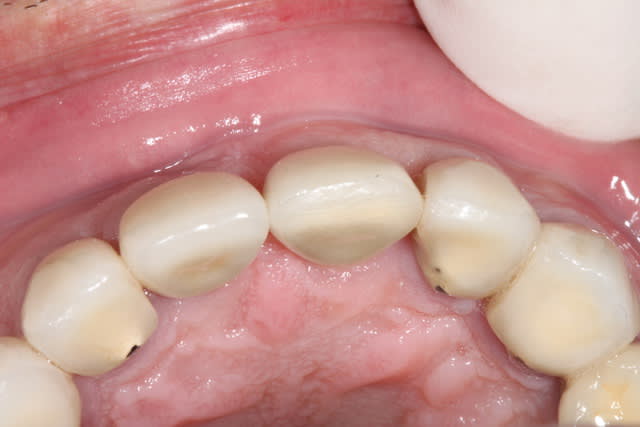

1/ photo pré op

photo de controle vue vestibulaire et occlusale 8 mois post chir

puis à 2 ans post op

on constate que contrairement à la 11 surlaquelle il y a un affaissement de l'os vestibulaire

sur la 21 le volume est préservé